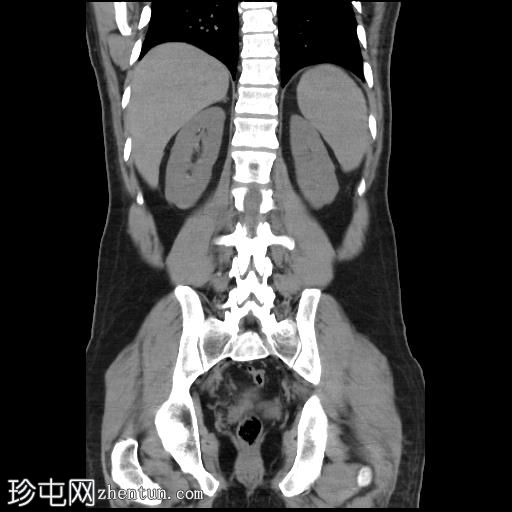

轴位增强扫描(门静脉期)

CT扫描显示胰腺组织完全包绕十二指肠第二段。未发现胰周结节或肿块。

此外,右肝VII段可见一低密度病灶,呈结节状强化,直径达12 mm,提示肝血管瘤。

左肝II段可见一强化病灶,提示快速充盈型血管瘤。

此外,肝实质内可见少量低密度病灶,但体积过小,无法准确定性。